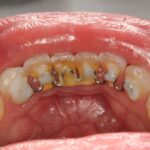

O consumo de açúcar é um dos maiores facilitadores do desenvolvimento de cáries dentárias.

Isso acontece porque, ao ser ingerido, ele serve de alimento para bactérias presentes naturalmente na boca. Essas bactérias produzem ácidos que corroem o esmalte dentário, provocando a desmineralização e, com o tempo, a formação das cáries.

Muita gente só percebe a cárie quando sente dor ou os dentes apresentam buracos visíveis. Afinal de contas, ela evolui muitas vezes de forma silenciosa, destruindo gradualmente as estruturas dentárias. A dor nem sempre é um sintoma imediato, o que faz com que muitos adiem a visita ao dentista, e isso pode agravar ainda mais o quadro.